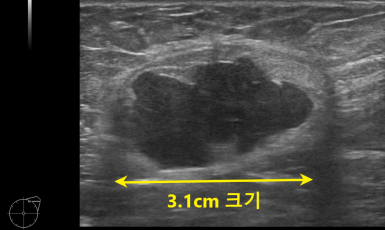

246번째 유방암 진단사례 (2019년3월6일) 수개월전부터 오른쪽 가슴에 단단한 멍울이 만져졌으나 대수롭지 않게 생각하고 지내오시다가 가족이 발견한 후에 진료 권유받고 ..

244번째 유방암 진단사례 (2019년2월14일) 수개월전부터 왼쪽 겨드랑이에 멍울이 만져져 내원한 환자분이셨습니다. 올해 1월에 다른 병원에서 검사한 공단..